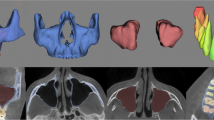

Anterior cranial base (ACB) is known as the growth-stable structure. Automatic segmentation of the ACB is a prerequisite to superimpose orthodontic inter-treatment cone-beam computed tomography (CBCT) images. The automatic ACB segmentation is still a challenging task because of the ambiguous intensity distributions around fine-grained structures and artifacts due to the limited radiation dose. We propose a fully automatic segmentation of the ACB from CBCT images by a volumetric convolutional network with nested residual connections (NRN). The multi-scale feature fusion in the NRN not only promotes the information flows, but also introduces the supervision to multiple intermediate layers to speed up the convergence. The multi-level shortcut connections augment the feature maps in the decompression pathway and the end-to-end voxel-wise label prediction. The proposed NRN has been applied to the ACB segmentation from clinically-captured CBCT images. The quantitative assessment over the practitioner-annotated ground truths demonstrates the proposed method produces improvements to the state-of-the-arts.